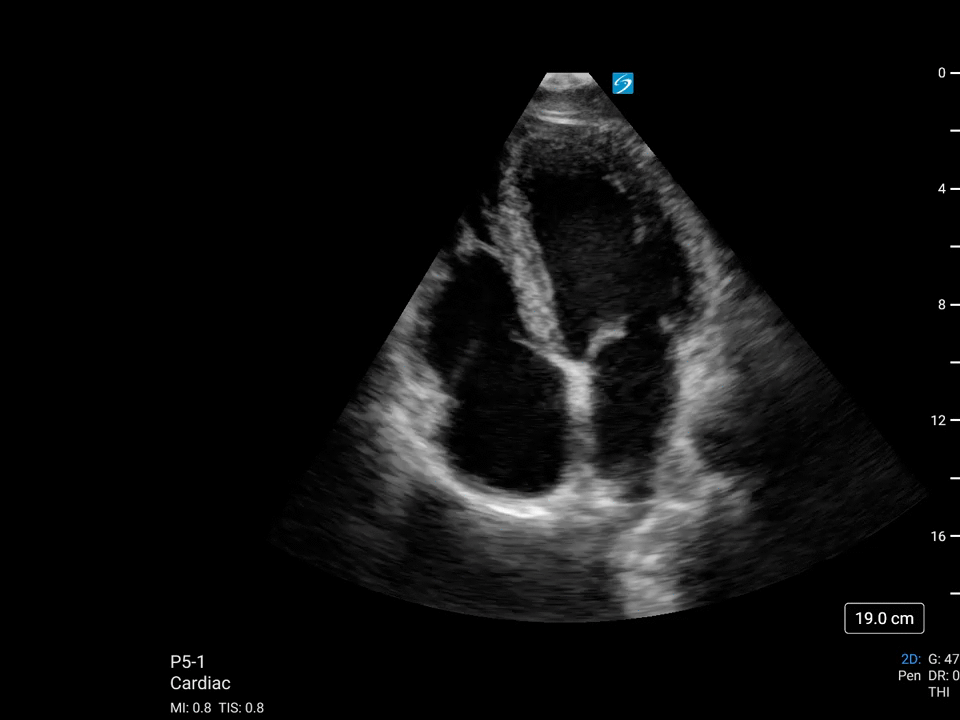

Sonosite PX, hastaları tedavi ederken ve teşhis ederken güven için en gelişmiş görüntü netliğimizi bünyesinde barındırır. Arayüz, geliştirilmiş verimlilik için dokunmatik ve fiziksel kontrolleri bir araya getirirken, uyarlanabilir yataydan dikeye çalışma yüzeyi optimum yatak başı ergonomisi sağlar. Sonografik dönüm noktalarını daha doğru bir şekilde görselleştirmek için Sonosite’in en gelişmiş görüntü netliği ve optimum hasta bakımı için ses kontrolü.

Üstün Görüntü Kalitesi

Daha iyi görüş, daha derin anlayış. Sonosite, klinisyenlerin en zorlu ihtiyaçlarını karşılamak için yeni bir görüntü performansı standardını yeniden tanımlıyor.